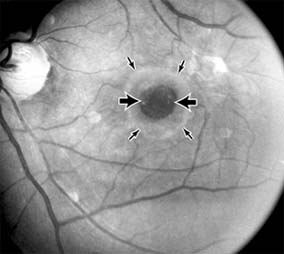

MACULAR EDEMA

Retinal edema involving the macula may be associated with a variety of intraocular inflammatory diseases, retinal vascular diseases, intraocular surgery, inherited or acquired retinal degenerations, medications, macular membranes, or unknown causes. Macular edema may be diffuse, with nonlocalized intraretinal fluid causing thickening of the macula. When edema fluid accumulates in honeycomb-like spaces of the outer plexiform and inner nuclear layers, it is called cystoid macular edema. On fluorescein angiography, fluorescein dye leaks from the perifoveal retinal capillaries and accumulates in a flower-petal pattern about the fovea (Figure 10-4).

Figure 10-4

Figure 10-4: Flower-petal pattern of fluorescein dye in a patient with cystoid macular edema after cataract surgery.